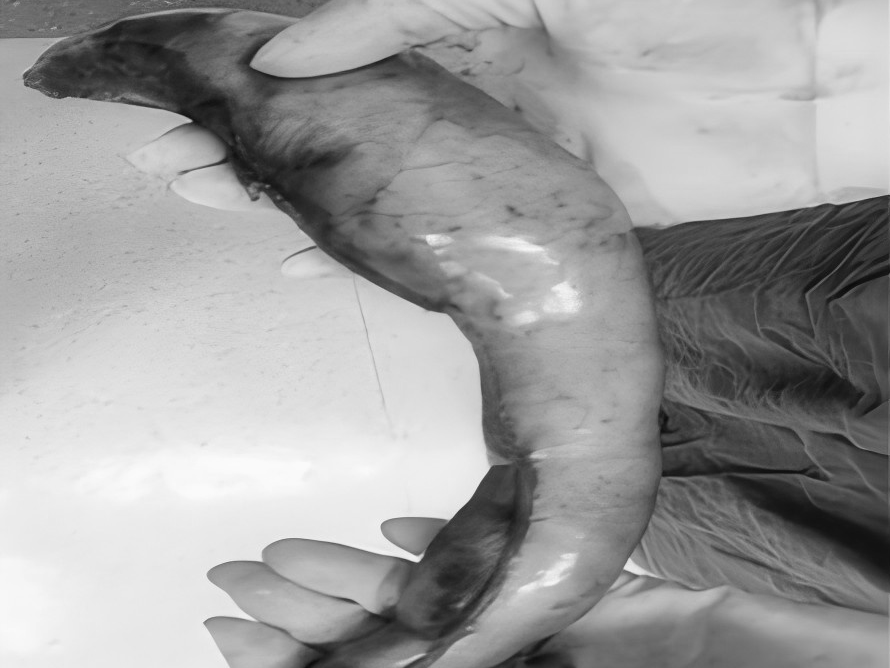

多年来,贵州航天医院各科室紧跟医学前沿,不断强技术、补短板,大力开展新技术、新项目,完成了许多高精尖、高难度、本地区“首例”的技术,填补了医院医疗技术空白,满足了群众日益增长的医疗需求。 本期,我们将为大家带来普外科特色技术——腹腔镜下腹股沟疝无张力修补术(TAPP)。 案例分享 患者在两年前检查发现双侧腹股沟区可复性包块,因当时症状较轻,偶有疼痛,患者未予重视,最近几个月,疼痛愈发频繁,严重影响了工作和生活,故前来我院普外科就诊。科室为患者完善了超声等相关检查后,明确诊断为:双侧腹股沟疝。 在充分与患者进行沟通同意后,制定并成功实施了腹腔镜下腹股沟疝无张力修补术治疗的方案,术中出血量少,术后第三天顺利出院。 腹腔镜下腹股沟疝无张力修补术(TAPP)能在无张力的情况下,利用人工高分子材料网片进行修补,具有术后疼痛轻、恢复快、复发率低等优点,已成为目前患者选择最多的疝修补术。 什么是腹腔镜下腹股沟疝无张力修补术 像用“补丁”补衣服一般,用人体组织兼容的高分子材料进行“补片”,由于不是强行拉合疝洞两边的组织,而是将补片覆盖腹股沟疝的缺损,所以组织间不产生张力,最大限度地保留了人体原有的生理结构和组织层次。同时,补片多呈网状结构,能起到支架作用,使人体自身的组织沿着补片支架生长。 腹腔镜下腹股沟疝无张力修补术原理 通过三个仅0.5 -1cm 的小切口进入腹腔,打开腹膜后将疝囊回纳,利用腹腔镜和专用器械在腹膜前间隙植入补片,覆盖肌耻骨孔,关闭腹膜后完成疝修补操作,有效减小了患者手术创伤。 腹腔镜下腹股沟疝无张力修补术优势 (一)修补结实,损伤更小。 (二)具有符合生理学的优势,术后不适感减少。 (三)保持局部组织结构层次,为再发疝或其他疾病留下治疗余地。 (四)能全面观察病情,发现无明显症状的隐匿疝,避免遗漏。 贵州航天医院普外科专家团队 梁 跃 中共党员,普外科党支部书记、主任,主任医师 临床擅长:对普外科各类肿瘤手术具有丰富的临床经验。 毕业于遵义医学院,遵义市医学会小儿外科学分会常务委员,遵义市肛肠协会理事,遵义市医学会核医学分会(第二届)委员会委员;荣获第三期“黔医人才计划”优秀学员称号;主持市级课题1项,完成省级课题1项,在国内各类刊物上发表论文10余篇。 钱科洪 民盟盟员,普外科副主任医师 临床擅长:从事普外科临床工作30余年,对各类普外科疾病的诊治、乳腺、甲状腺、胃十二指肠、结直肠等疾病及疑难杂症具有丰富的临床经验。 毕业于遵义医学院临床医疗系,2009年前往中山大学附属第一医院微创外科进修学习,在国内各专业期刊发表论文数篇。 贵州航天医院普外科简介 基本情况 贵州航天医院普外科成立于1968年,前身属于航天部O61基地3417医院外一科,1998年3417医院、3427医院合并后更名为普外科,下设胃肠外科、肛肠外科2个亚专业科室,拥有在全市较为先进的专科设备和技术,是中国疝病专科联盟单位,贵州医科大学附属医院胃肠外科专科联盟单位。开放床位40张,配备医护人员21人。 专科特色 普外科致力于胃肠及肛肠疾病的外科临床诊治及科研,以腹腔镜微创外科技术为本,形成以快速康复治疗胃肿瘤、结直肠肿瘤、小肠肿瘤、直肠脱垂、肥胖病、急腹症、各类疝、痔、瘘等专科特色,同时注重胃肠疾病尤其是结直肠恶性肿瘤的基础研究和临床转化研究,总体诊断和治疗水平在区域同级医院居于领先水平。 开展手术:腹腔镜下胃癌根治术,腹腔镜下袖状胃切除术,腹腔镜下胃肠道间质瘤切除术,腹腔镜下结、直肠癌根治术,胃癌、结直肠癌的精准治疗,腹腔镜下小儿疝气、成人疝修补术,腹腔镜下阑尾手术,内痔的硬化注射治疗及痔疮的微创治疗:ATH、PPH、TST,直肠脱垂的各种手术治疗,难治性伤口VSD技术,鼻胃肠管、肠梗阻导管置入术,肛肠术后间歇性导尿技术,并引进了中医适宜技术,也为各种化疗患者提供输液港安装,提高患者就医体验。 腹腔镜下腹股沟疝 无张力修补术 腹股沟疝里金斯坦(Lichtenstein)手术 PPH微创术治疗环状混合痔 黏连性或炎性肠梗阻-肠梗阻导管 腹腔镜袖状胃切除 腹腔镜阑尾切除术 腹腔镜阑尾肿瘤切除术 腹腔镜下结肠癌根治术 诊疗范围 胃肿瘤、结直肠肿瘤、小肠肿瘤、肥胖症、各类急腹症、腹部外伤、腹壁疝、便秘、直肠脱垂、痔疮、肛瘘、肛裂等胃肠、肛肠外科疾病。 一审一校:梁 跃、黄成成